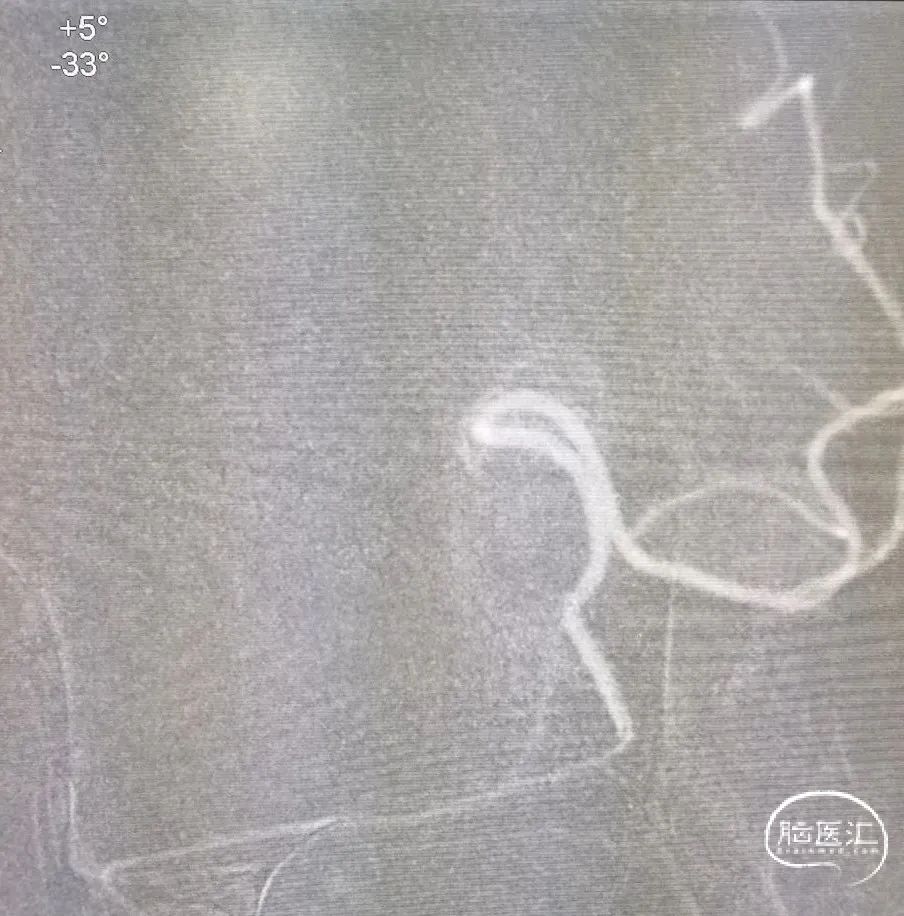

4*30mm Syphonet®取栓支架释放后路图。

大脑中动脉取栓一把通。